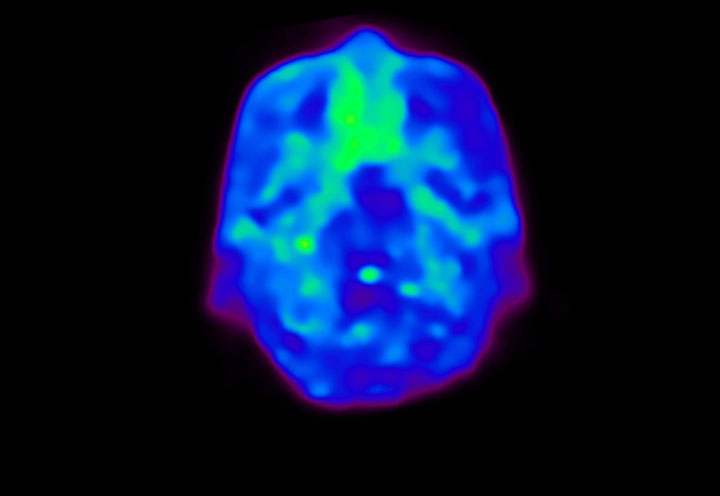

Head / Case4 : Amyloid

Courtesy : Kindai University Hospital

- Injected dose: 3.21 MBq/kg, 18F-Flutemetamol

- Uptake time: 100 minutes

- Scan time: 20 minutes